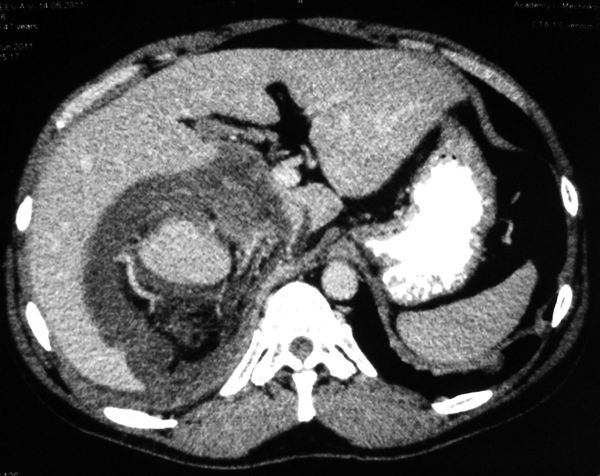

Огромная опухоль правой почки

Гигантская опухоль правой почки. Экстримальная нефрэктомия.